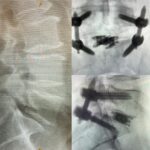

T/PLIF Solutions

T/PLIF

Heights 7mm* expanding to 17mm*

Width 12mm expanding to 21mm

0°, 8°, 12° and 15° Lordosis*

TLIF